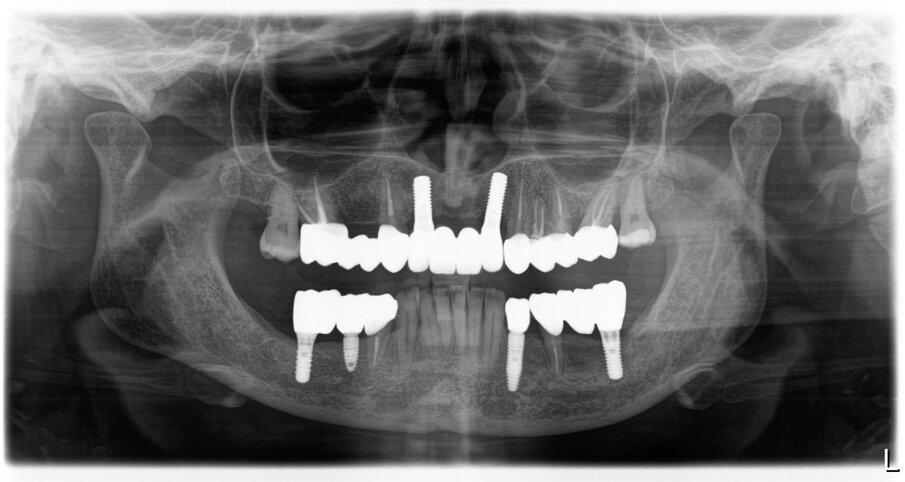

Fig. 50_Radiografia iniziale

Fig. 51_Radiografia a 5 anni dalla consegna del lavoro. Ai follow-up vengono eseguite annualmente delle rx endorali centrate, e alla necessita viene ripetuta un’opt.